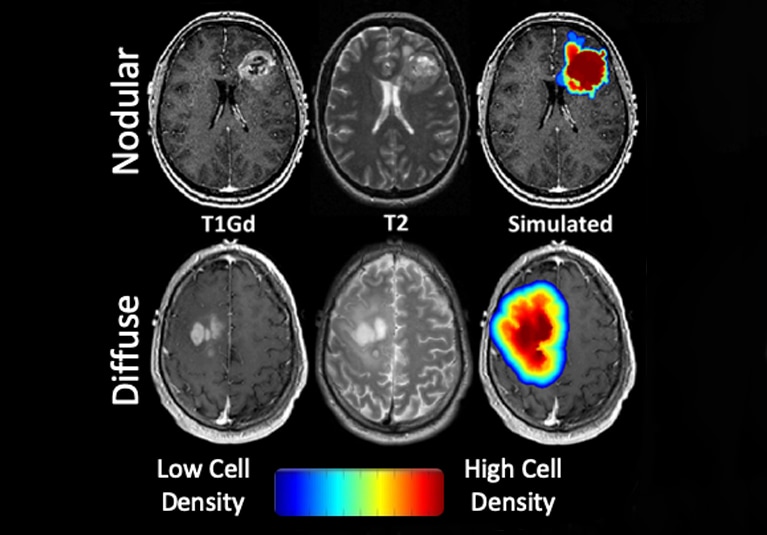

The temozolomide study compared gadolinium-enhanced T1-weighted and T2 fluid-attenuated inversion recovery images taken before and after adjuvant treatment. The images were used to determine volumetric changes in imaging abnormalities and to calculate a tumor invasion metric based on mathematical modeling.

تُظهر الصور الموزونة T1 وصور استعادة الانعكاس المخفف بالسوائل T2 المعززة بالغادولينيوم مستويات مختلفة من الكثافة في الأورام الأرومية الدبقية. يَظهر اللون بشكل أخف في الورم العقيدي في الصف العلوي، بينما يشير اللون الأوضح إلى الحجم الأكبر لخلايا الورم الموجودة في خزعة الورم المنتشر الموضح في الصف السفلي.

As described in the March 2020 issue of PLOS One, nodular tumors tended to respond more favorably to adjuvant temozolomide, in terms of both volumetric change and patient outcomes. "The less invasive the tumor looks, the greater the decrease in tumor volume and the longer the patient will have a sustained response to temozolomide," Dr. Swanson says.

She notes that the greater response in nodular tumors might be due to higher concentrations of temozolomide in the tumor core, where the blood-brain barrier is likelier to be compromised compared with surrounding tissue. "In a diffuse glioblastoma, the tumor cells have migrated so far that the blood-brain barrier is still intact in those regions," Dr. Swanson says. "The drug is not going to get there."